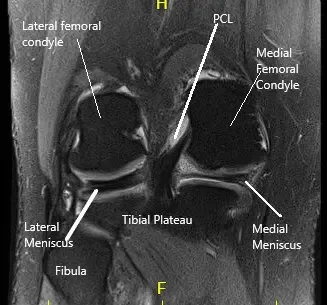

MRI of the right knee suggested a large bucket-handle tear of medial meniscus, displaced into the intercondylar notch and over the anterior horn.

MRI of the right knee in the sagittal and coronal section.